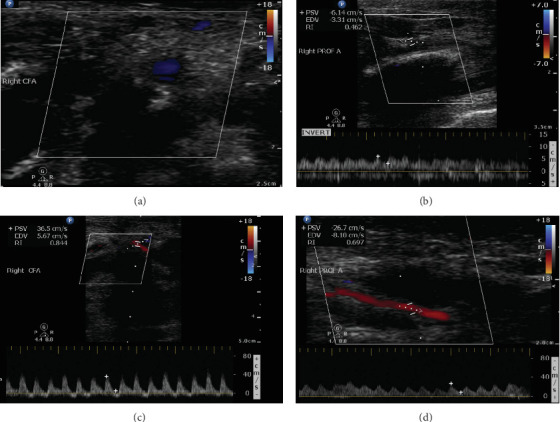

Acute limb ischemia (ALI) in neonates is a rare but critical condition often resulting from iatrogenic causes, such as arterial catheterization. This case highlights the unique challenges in diagnosing and managing ALI in this population, where evidence-based guidelines are scarce and treatment decisions rely heavily on expert consensus and extrapolation from adult data. We report the case of a premature neonate, born at 30 weeks' gestation, who developed ALI secondary to femoral artery thrombosis following arterial line insertion. The patient presented with bluish discoloration, diminished capillary refill, and absent distal pulses in the affected limb. Duplex ultrasonography confirmed occlusion of the right common femoral artery. Conservative management with anticoagulation and close observation was adopted by multidisciplinary consensus involving neonatology and vascular surgery. Despite signs of worsening ischemia and skin necrosis during therapeutic anticoagulation, the team opted to continue conservative management due to the high surgical risk posed by the patient's prematurity and multiple comorbidities. Over the next week, gradual clinical and imaging improvements were noted, including recanalization of the occluded artery and restoration of arterial flow, ultimately leading to successful limb salvage. This case underscores the importance of individualized, multidisciplinary decision-making in managing neonatal ALI. Conservative management with therapeutic anticoagulation can achieve favorable outcomes, even in cases with worsening ischemia, provided that close monitoring and optimal supportive care are ensured. It also highlights the need for further research to develop standardized pediatric guidelines for this rare but potentially devastating condition.